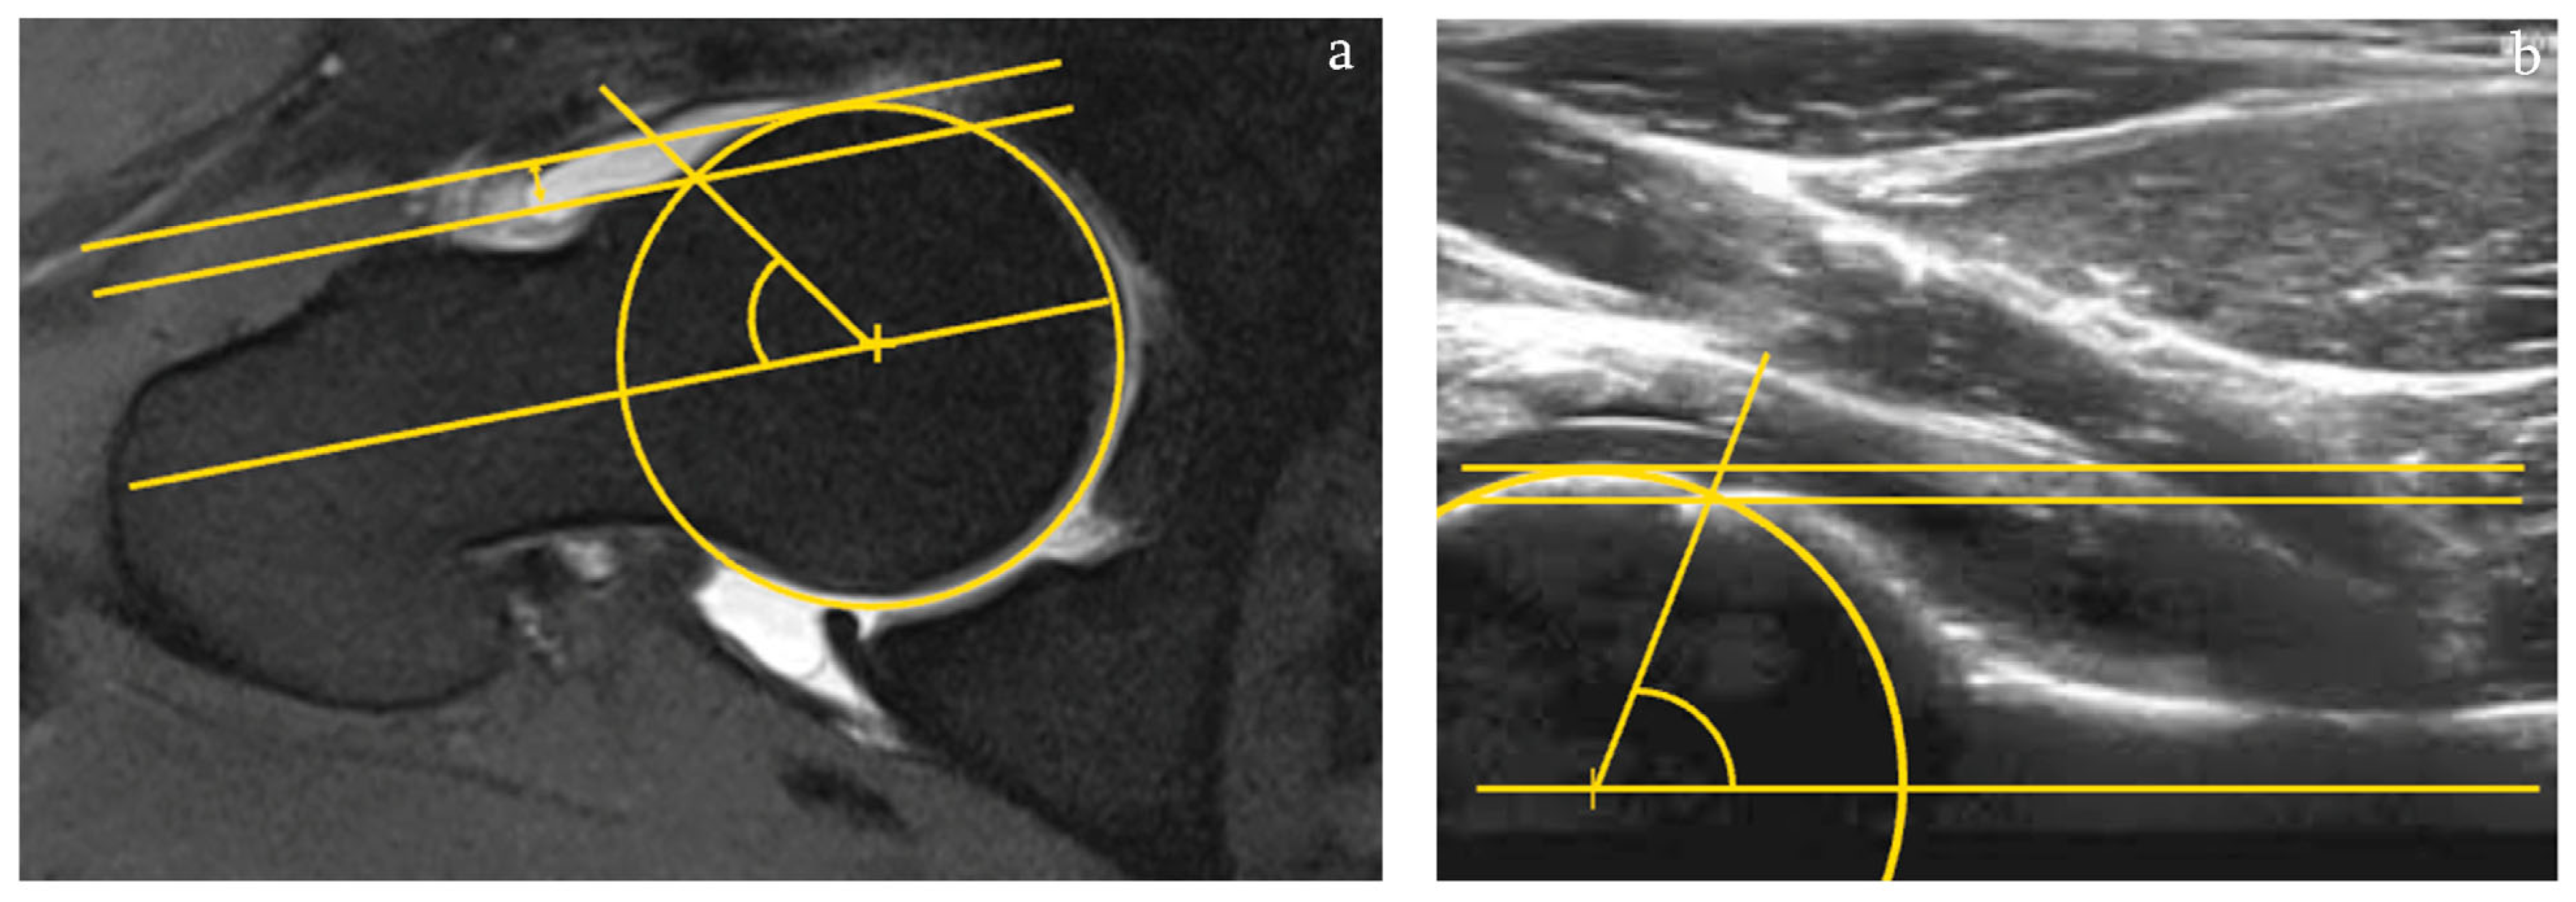

2.3.1. Evaluation of Anterior Alpha Angle

For ultrasound-assisted evaluations of the anterior alpha angle first, the center of the femoral head was identified using the circle tools of Weasis DICOM medical Viewer, 2020. The first arm of the angle was positioned as a line along the axis of the horizontally aligned femur. The second side of the angle was positioned as a line through the previously defined center of the head and the point where the shape of the femoral head changes into an aspherical shape, according to Noetzli et al. []. The same software and technique were used for the MR-tomographic determination of the alpha angle. The image showing the biggest plain head diameter with the largest cam deformation was used for the measurement (Figure 1a).

Figure 1.

Evaluation of the anterior alpha angle and anterior head–neck offset in arthro-MRI in axial section (a) and in ultrasound in anterior longitudinal section according to DEGUM guidelines (b).

2.3.2. Evaluation of the Anterior Head–Neck Offset

Just as for the evaluation of the alpha angle, in the sonographs, we first identified the femoral neck axis and the center of the femoral head. According to Eijer et al., a tangent to the highest expression of the femoral head and parallel to the neck axis was drawn using the same software mentioned above []. The femoral head segment was expanded to a full circle, and the spot where the femoral head leaves the sphericity was identified. Another parallel line to the femoral neck axis passing through this point was drawn. Then, the distance between these two lines was measured for the anterior head–neck offset [,,]. The same software and technique were used for the MR-tomographic assessment of the anterior head–neck offset (Figure 1b).